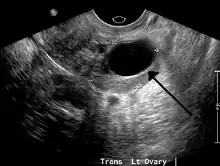

Ovarian cysts are usually diagnosed by ultrasound, CT scan, or MRI, and correlated with clinical presentation and endocrinologic tests as appropriate.[10]

Ultrasound

Follow-up imaging in women of reproductive age for incidentally discovered simple cysts on ultrasound is not needed until 5 cm, as these are usually normal ovarian follicles. Simple cysts 5 to 7 cm in premenopausal females should be followed yearly. Simple cysts larger than 7 cm require further imaging with MRI or surgical assessment. Because they are large, they cannot be reliably assessed by ultrasound alone; it can be difficult to see posterior wall soft tissue nodularity or thickened septation due to limited ultrasound beam penetrance at this size and depth. For the corpus luteum, a dominant ovulating follicle that typically appears as a cyst with circumferentially thickened walls and crenulated inner margins, follow up is not needed if the cyst is less than 3 cm in diameter. In postmenopausal patients, any simple cyst greater than 1 cm but less than 7 cm needs yearly follow-up, while those greater than 7 cm need MRI or surgical evaluation, similar to reproductive age females.[11]

For incidentally discovered dermoids, diagnosed on ultrasound by their pathognomonic echogenic fat, either surgical removal or yearly follow up is indicated, regardless of patient age. For peritoneal inclusion cysts, which have a crumpled tissue-paper appearance and tend to follow the contour of adjacent organs, follow up is based on clinical history. Hydrosalpinx, or fallopian tube dilation, can be mistaken for an ovarian cyst due to its anechoic appearance. Follow-up for this is also based on clinical presentation.[11]

For multiloculate cysts with thin septation less than 3 mm, surgical evaluation is recommended. The presence of multiloculation suggests a neoplasm, although the thin septation implies that the neoplasm is benign. For any thickened septation, nodularity, vascular flow on color doppler, or growth over several ultrasounds, surgical removal may be considered due to concern of cancer.[11]